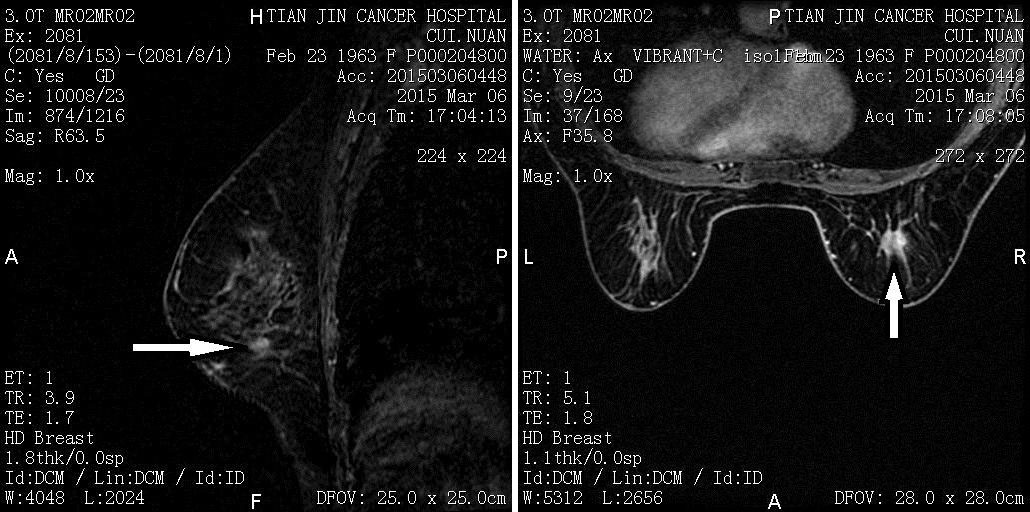

新辅助化疗后MRI

*箭头处原发病灶消失

*箭头所指为内乳区淋巴结残留影像

*箭头所指为腋窝淋巴结残留影像